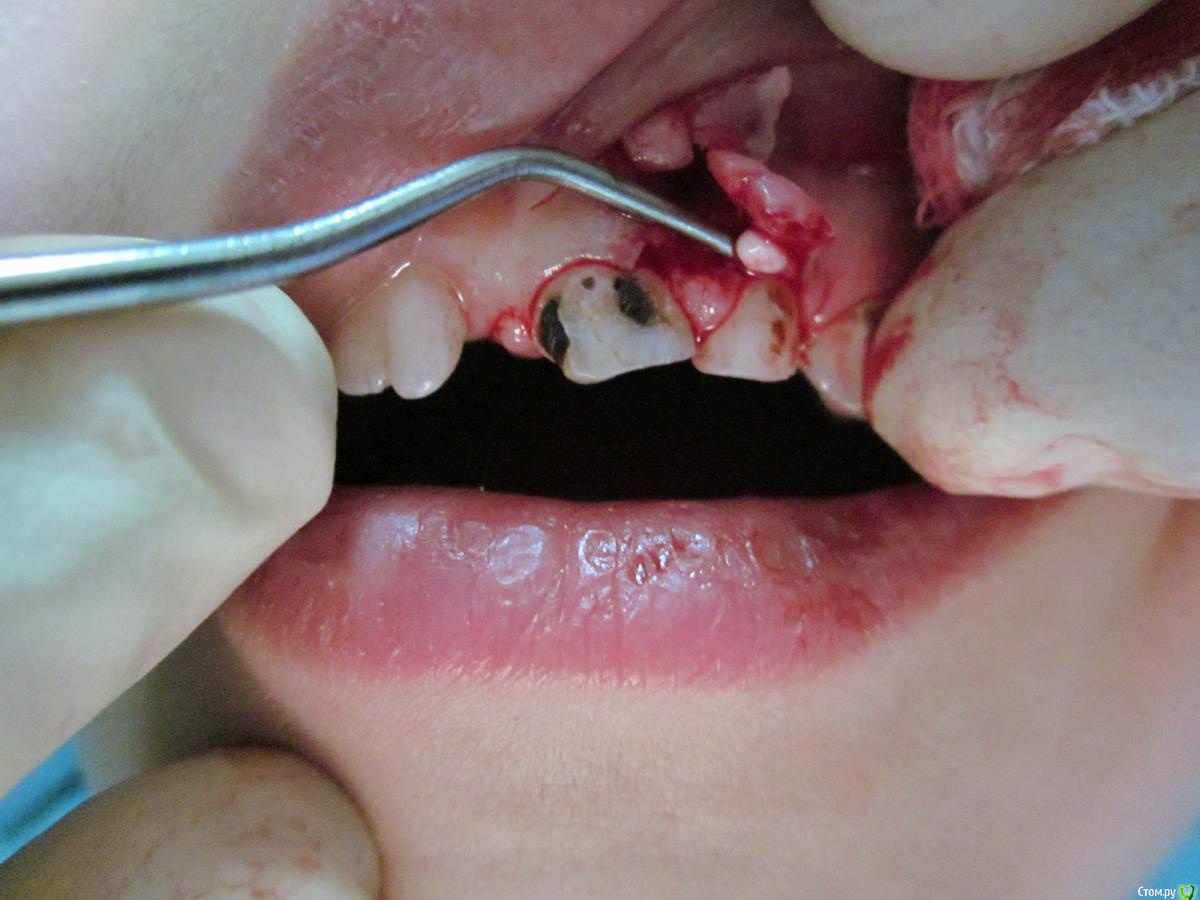

По данному случаю: пациент 6-7 лет, 21 не растёт, все динамят (ортодонты и терапевты), дошли до хирурга: на снимок прицельный, что то не то, на КТ охарактеризовал как одонтому. Операция под

анестезией Ультракаин дс, кортикальную пластинку трепанировал «расковырял» эскаватором, убрал конгломерат тведых тканей, саму оболочку, удалил 61. Биологический материал в пробирку с физ

раствором, направление на исследование в гистологию и ГОУ самим.

На перевязках ничего особенного, швы убрал на 7–е сутки, результаты анализов не принесли, и потом пропали. Прорезался 21 или не не знаю, вызвонивать не стал.